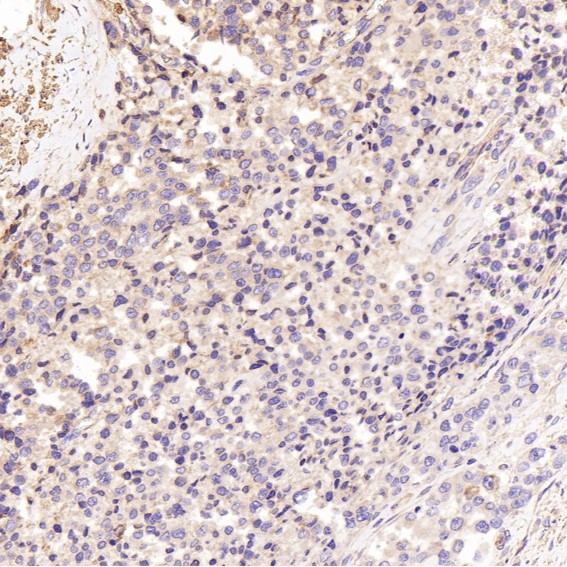

Immunohistochemical analysis of paraffin-embedded Human small cell lung cancer , using the Antibody.

Immunohistochemical analysis of paraffin-embedded Human prostate cancer, using the Antibody.

Immunohistochemical analysis of paraffin-embedded Human pancreatic cancer, using the Antibody.

Immunohistochemical analysis of paraffin-embedded Human small cell lung cancer , using the Antibody.

Immunohistochemical analysis of paraffin-embedded Human prostate cancer, using the Antibody.

Immunohistochemical analysis of paraffin-embedded Human pancreatic cancer, using the Antibody.